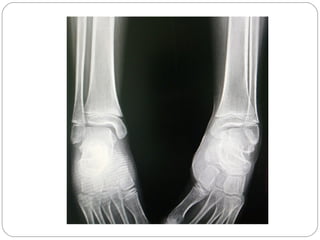

RADIOGRAFIA

ASTRAGALO 3-A´s

Abajo, Adelante, Adentro

ALTERACION FUNDAMENTAL

ARTICULACION SUBASTRAGALINA